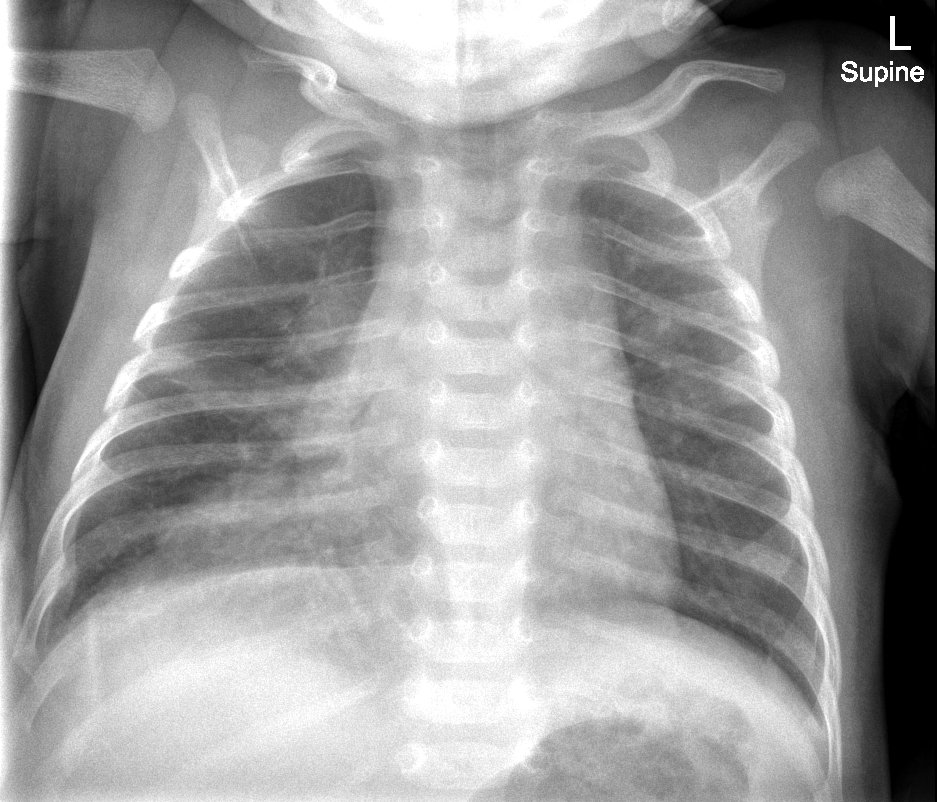

Infant tuberculosis (TB) is a rare but potentially deadly infection and difficult to diagnose, especially in infants who may present with non-specific symptoms. Here, we report a case of an United States-born term infant with community-acquired miliary TB and no confirmed TB exposure history. The patient initially presented with respiratory distress at seven weeks of life with chest radiograph showing a right lower lobe (RLL) infiltrate. After failing multiple courses of treatment for community-acquired pneumonia and developing growth faltering, the patient had imaging findings suggestive of TB infection with CNS involvement. The diagnosis of TB was confirmed by QuantiFERON and purified protein derivative (PPD). In infants who fail conventional treatment for bacterial pneumonia, the differential should be broadened to consider alternative etiologies. Additionally, brain imaging should be performed in cases of disseminated TB despite negative cerebrospinal fluid (CSF) studies since these patients are at high risk of central nervous system (CNS) involvement.